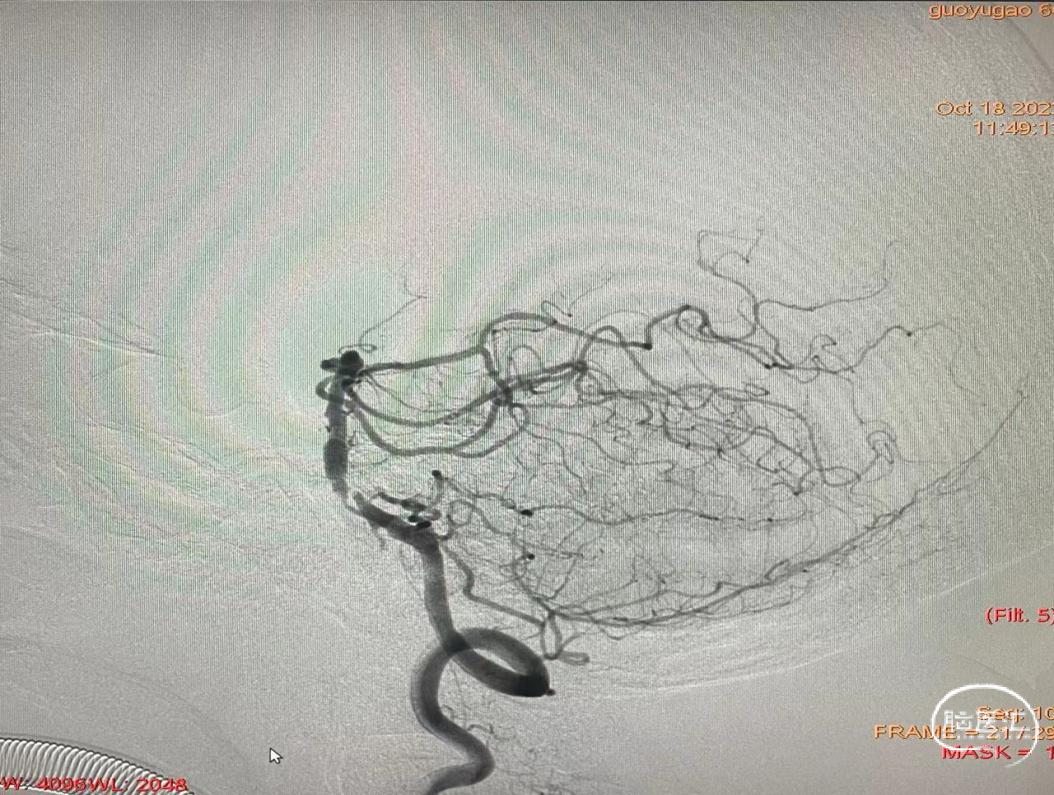

支架释放后,工作位造影血流通畅。

术后恢复:患者术后恢复良好,症状缓解。

椎基底动脉重度狭窄的治疗,血管走形迂曲,导致治疗困难,稳定的通路建立对于手术的成功至关重要。术中使用通桥银蛇®TGC 颅内支持导管,建立稳定可靠的通路。

对于血管走形迂曲,展示出优异的通过性,高到位接近病变位置。

优秀的支撑力为手术提供稳定、可靠的通路,为手术成功提供保障。